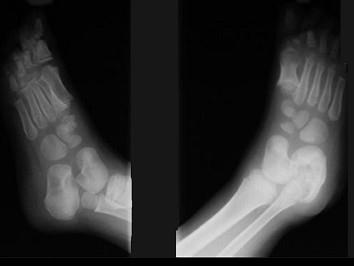

女,5岁,左踝疼痛,请结合图像,选出最可能的诊断 ( )A、风湿性关节炎B、痛风C、退行性骨关节病D、神经性关节病E、创伤性关节炎

问题 女,5岁,左踝疼痛,请结合图像,选出最可能的诊断 ( )

选项 A、风湿性关节炎 B、痛风 C、退行性骨关节病 D、神经性关节病 E、创伤性关节炎

答案 D